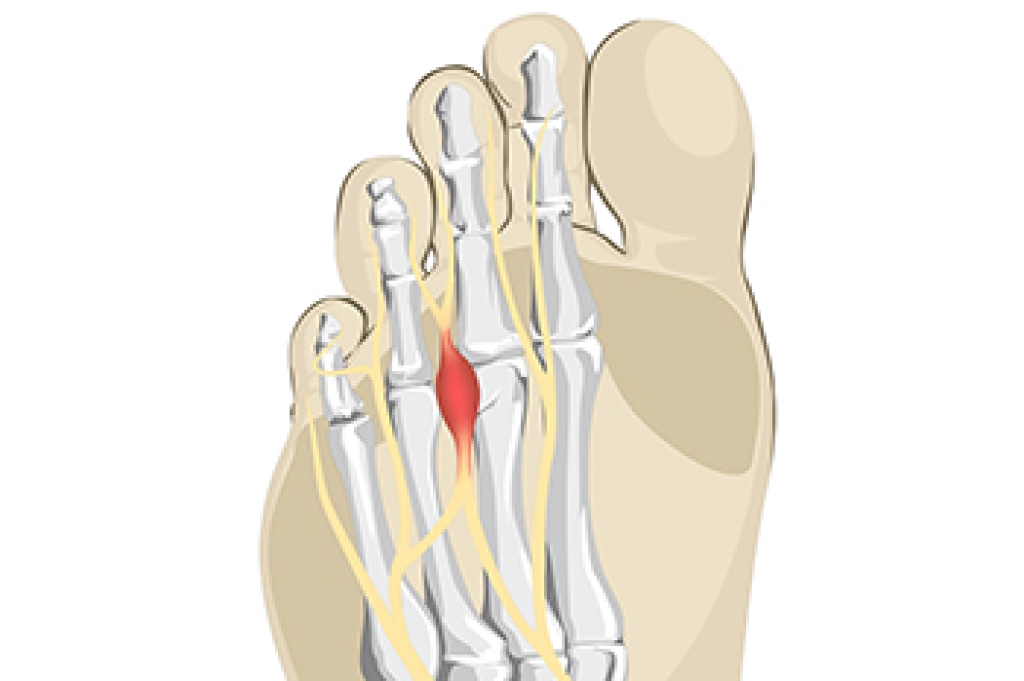

There are various types of injuries that can affect the Achilles tendon. The two most common injuries are Achilles tendinitis and ruptures of the tendon.

Achilles Tendinitis Symptoms

- Inflammation

- Dull to severe pain

- Increased blood flow to the tendon

- Thickening of the tendon

Rupture Symptoms

- Extreme pain and swelling in the foot

- Total immobility